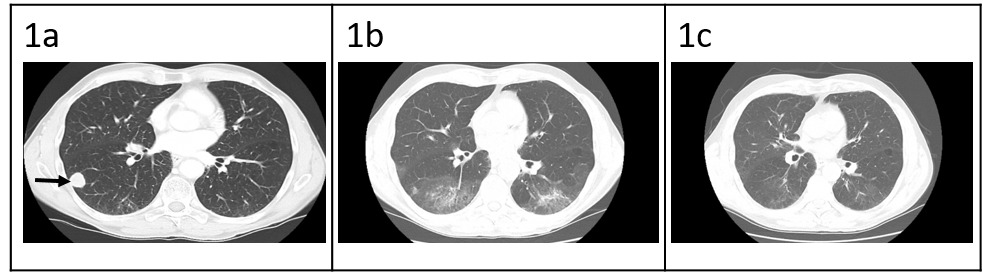

Patient is a 68-year-old male with prior history of nicotine dependence, chronic kidney disease (previous baseline creatinine ~1.3 to 1.4 mg/dL), and muscle invasive bladder cancer. He was initially diagnosed with Stage IIIA (cT3, cN0, cM0) disease3 in October 2019 and completed four cycles of neoadjuvant chemotherapy with gemcitabine and cisplatin followed by cystoprostatectomy.3 At time of surgical resection, he had persistent T3 disease. One year later, he was found to have metastatic recurrence to the lungs, right hilar nodes, and perineum (Figure 1a). The National Comprehensive Cancer Network guidelines for first-line therapy of metastatic bladder cancer is determined by cisplatin eligibility.3 In this patient with a prior poor response to neoadjuvant cisplatin-based chemotherapy, pembrolizumab monotherapy was chosen as front-line treatment for metastatic disease. After 10 cycles, he was incidentally found to have grade 1 pneumonitis on routine CT scan (Figure 1b). Pembrolizumab was held, and he was treated with a 1-month course of prednisone 1 mg/kg. Repeat CT chest after completion of steroids showed improvement of pneumonitis and a near complete radiographic response of his cancer (Figure 1c). He was not re-challenged with further pembrolizumab.